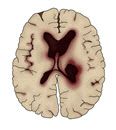

◇ 뇌졸중은 혈관이 막히거나 터져 뇌 조직이 손상되는 질환

뇌졸중은 혈관이 막히거나 터져서 뇌 조직이 손상되는 질환이다. 혈관이 막혀 뇌가 손상되면 ‘뇌경색’, 혈관이 터져서 뇌가 손상되면 ‘뇌출혈’로 분류된다. 뇌경색이 전체 뇌졸중의 80%를 차지한다. 뇌경색은 동맥경화(혈관 벽 내부에 지방 성분과 염증 세포가 쌓여 동맥이 딱딱하게 굳어지는 상태)가 주원인이 되어 발생한다. 뇌혈관이 터져 출혈이 생기는 출혈성 뇌졸중은 20% 정도 된다. 뇌출혈 중에서는 고혈압에 의해 손상된 뇌혈관이 파열되는 뇌내출혈과 뇌혈관에 생긴 꽈리 모양의 동맥류가 터져 생기는 지주막하 출혈 등이 있다.